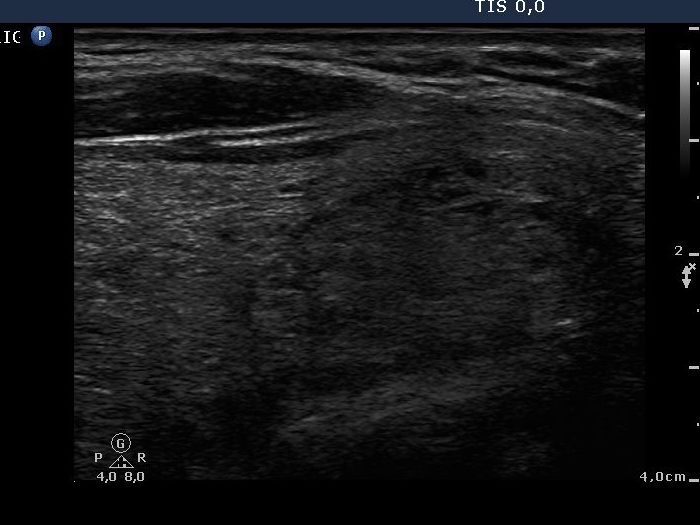

Benign nodular hyperplasia - Case 1. |

Clinical data: A 45-year-old man who was operated on a benign hyperplastic nodule 17 years ago. Ha had difficulties in swallowing in the last few months.

Palpation: an enlarged right lobe with multiple nodules.

Functional state: euthyroidim with TSH-level 1.43 mIU/L.

Ultrasonography: The right lobe was enlarged and had multiple small hypoechogenic lesions. There was a minimally hypoechogenic, larger nodule in the lower part of the lobe. The left lobe was resected.

Cytological diagnosis: benign colloid goiter.

The patient was operated because of compression sign caused by the recurrent goiter.

Histopathology disclosed benign, hyperplastic nodules.